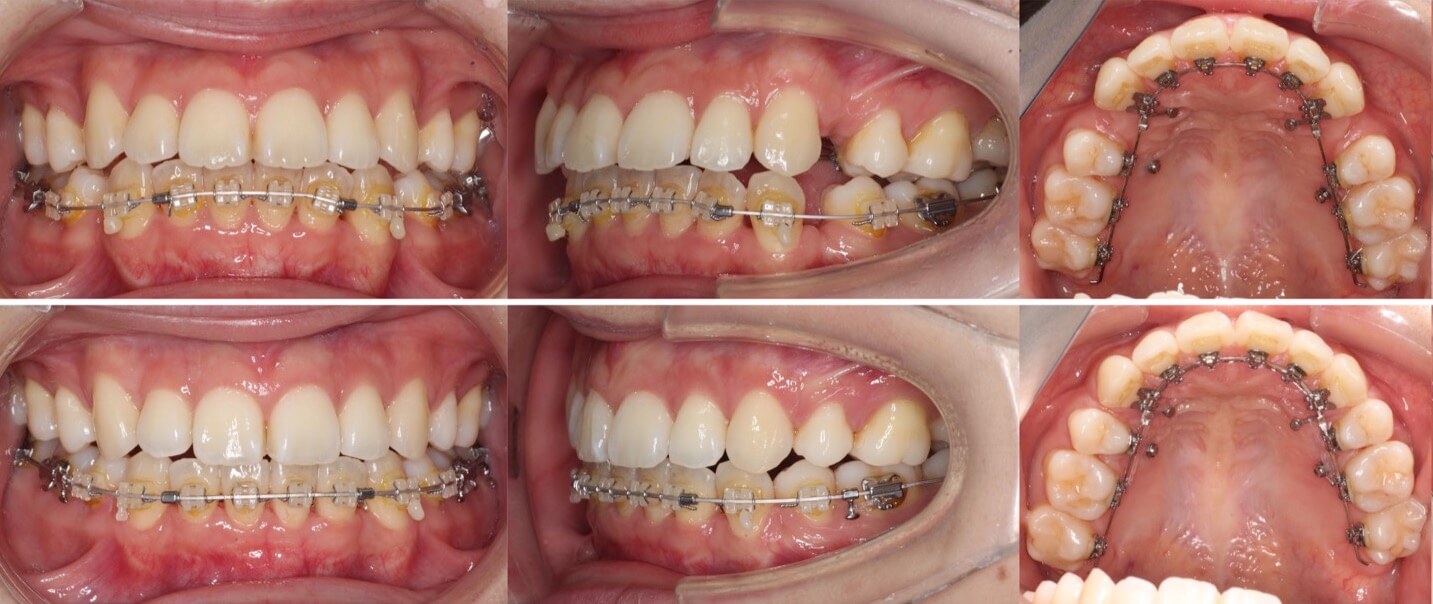

「男性は顔が引き締まる」

高校生男性・唇側矯正装置・下あご後退型

当初は、抜歯矯正治療にするかしないかで、治療方針に迷ったケースですが、最終的には患者さんの希望に沿って抜歯矯正治療にしました。歯の動きがゆっくりであったため、治療期間が3年を超えてしまいました。

<症例概要> 難易度:★★★★☆

主訴:口元の突出・前歯のガタツキ

年齢・性別:高校生男性

住まい:千葉県八千代市市

症状:下顎後退・叢生

治療方針:抜歯空隙の閉鎖(最大固定)

治療装置:唇側矯正装置

固定:歯科矯正用アンカースクリュー(頬側x2)

抜歯:上下第一小臼歯(計4本)

治療期間:3年4か月

リテーナー:上下プレートタイプ+フィックスタイプ

治療費用:968,000(税込)

代表的副作用:痛み・治療後の後戻り・歯根吸収・歯髄壊死・歯肉退縮